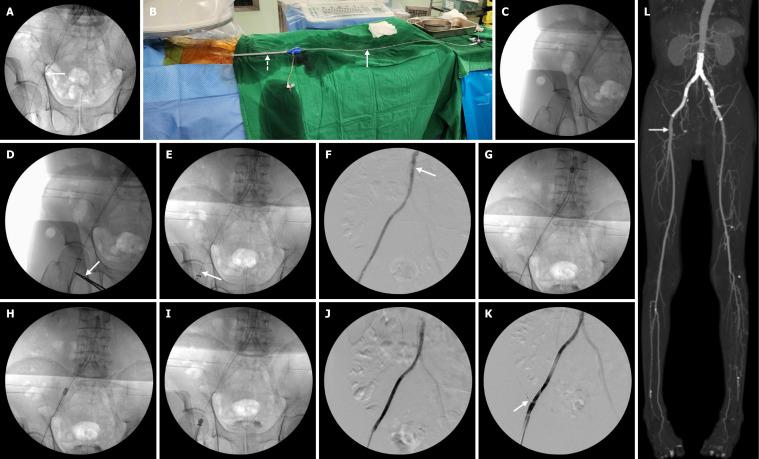

A 64-year-old male patient presented with severe claudication of the right leg. The patient's history included multiple prior interventions for aortoiliac lesions. The preoperative computed tomography (CT) imaging showed a thrombotic occlusion of right aortoiliac stenting. An Angiojet Omni thrombectomy catheter (Boston Scientific, Marlborough, MA, United States) was used to remove the thrombus in a retrograde fashion after the successful placement of the large-diameter sheath in the right common femoral artery for prevention of distal embolization. The remnant organized thrombus was removed with an over-the-wire Fogarty catheter (Edwards Lifesciences, Irvine, CA, United States). Completion angiogram and postoperative CT imaging demonstrated complete removal of thrombus and no evidence of distal embolization.

一名64岁男性患者出现严重的右腿间歇性跛行。该患者既往有多次主髂病变的介入治疗史。术前计算机断层扫描(CT)成像显示右主髂动脉支架血栓形成闭塞。在成功将大直径鞘管置入右股总动脉以预防远端栓塞后,使用Angiojet Omni血栓切除术导管(美国波士顿科学公司,马尔伯勒,马萨诸塞州)逆行清除血栓。用金属丝引导的Fogarty导管(美国爱德华生命科学公司,尔湾,加利福尼亚州)清除残余的机化血栓。血管造影完成和术后CT成像显示血栓已完全清除,无远端栓塞迹象。